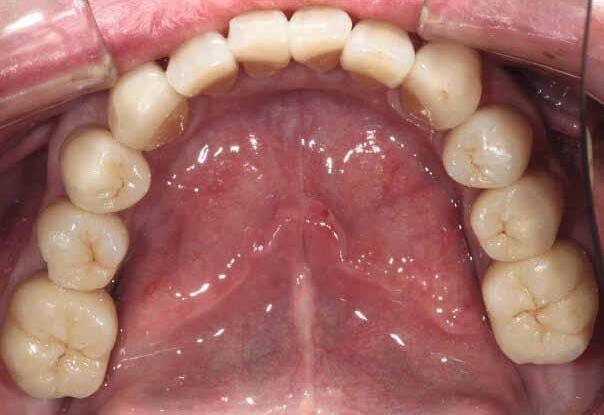

Restoring incisal wear and closing diastema with G-aenial A’CHORD. Courtesy of: Dr Aleksandra Slacan, Poland

Reshaping of teeth and diastema closure with G-aenial A’CHORD. Courtesy of: Dr Andres Silva, Spain